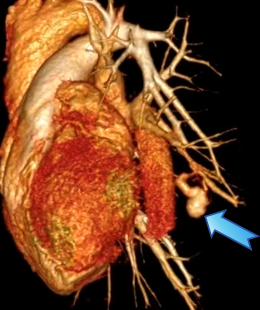

外院CT检查图像,箭头处为病灶

他们又赶往邻省另一家大医院,在接受抗感染治疗一周后,王女又出现两次明显咯血。复诊复查CT显示:结节由约1.6 cm增至约2.7 cm。当地医生再次建议尽快手术,认为可能需切除较大范围的左肺叶。由于病灶血供丰富,穿刺风险很高,所以难以获取病理。随后几天,夫妻俩辗转4家医院,答复几乎一致:必须手术切除。